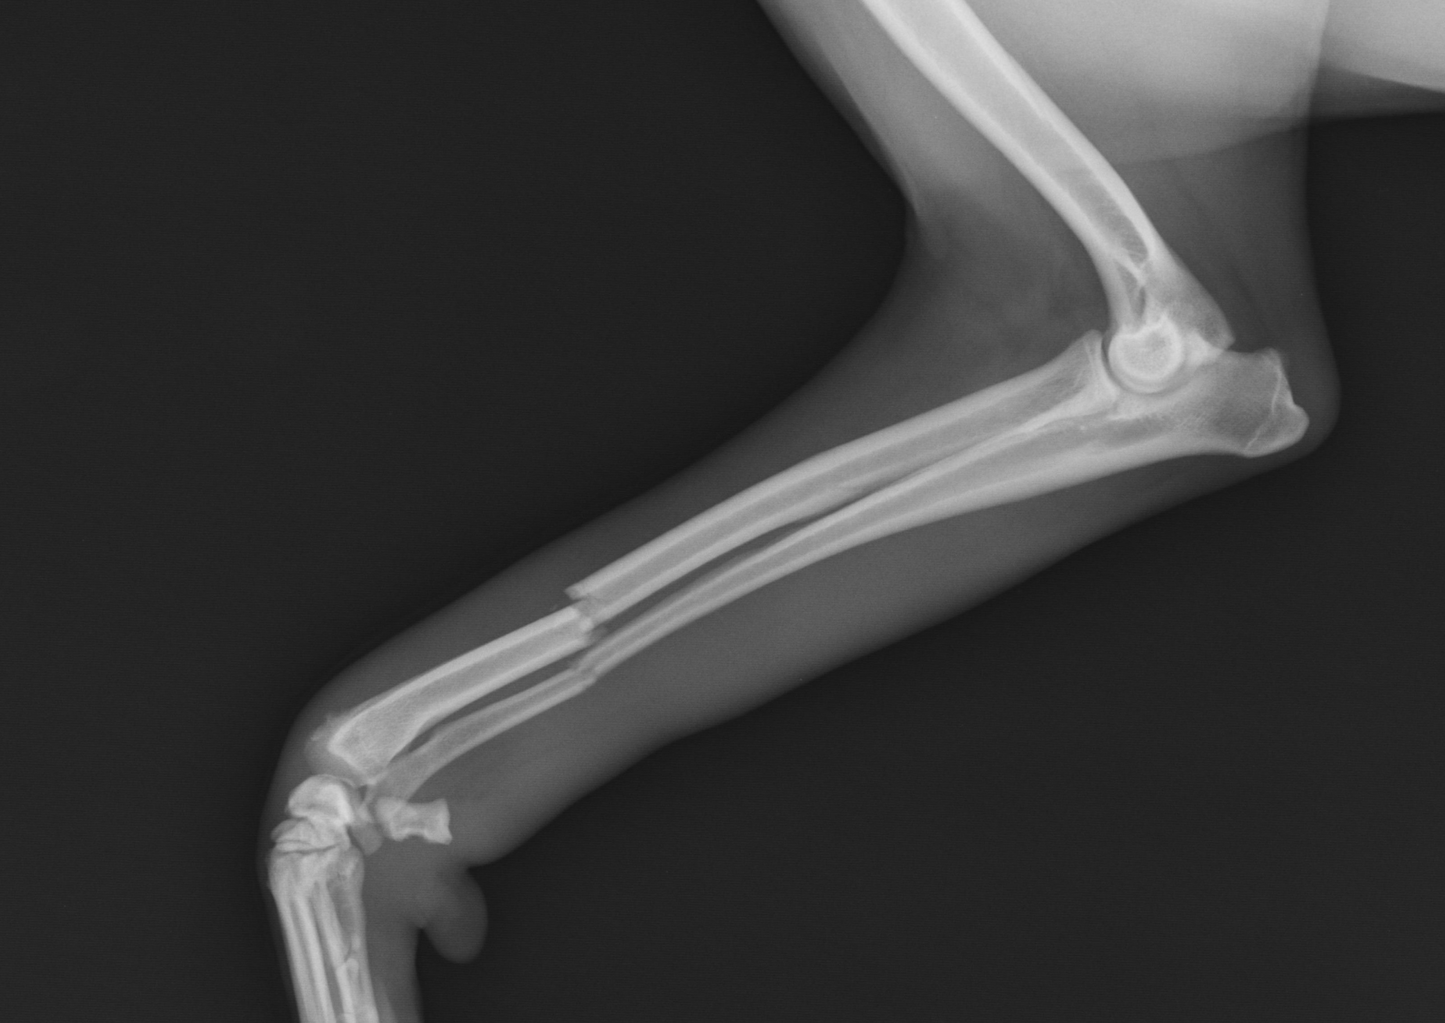

It is common knowledge that casting and splinting can be very harmful if done incorrectly. Casting can be very time consuming and ensuring the cast stays in place was difficult. Keeping a cast dry to prevent moisture and associated complications has been a challenge, moisture solutions are lacking, and owner compliance concerns are prevalent. Orthopets by Dassiet has re-engineered the casts, splints, and bandages common practice with a new concept for casting and splinting. We use the eco-friendly Woodcast biocomposite material and a textile called Unitex to produce the UPETS cast, splint, and bandage solutions. This novel system supports patients from toes to the humerus and femur respectively.Our professional team is a change maker the way animal casting and splinting will be done. Be brave and come to learn the UPETS way!